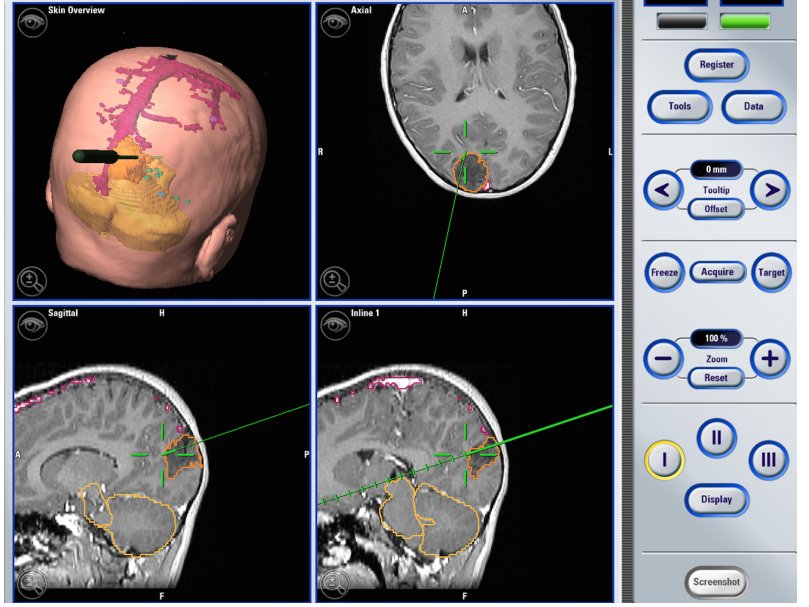

1所示。神經(jīng)導(dǎo)航工作站對(duì)一名12歲患有右側(cè)枕部腦瘤的男性進(jìn)行磁共振成像(MRI)的手術(shù)截圖。腫瘤用橙色標(biāo)出。綠線表示用于評(píng)估切除深度的在線探頭。在這種情況下,神經(jīng)外科醫(yī)生切除了腦腫瘤與正常大腦的接口。左上角描繪了皮膚概況和指向腫瘤的在線探針。神經(jīng)影像學(xué)、神經(jīng)導(dǎo)航、術(shù)中MRI和持續(xù)的神經(jīng)監(jiān)測(cè)方面的進(jìn)展促進(jìn)了神經(jīng)外科醫(yī)生切除人類腦瘤,同時(shí)較大限度地減少了對(duì)鄰近正常腦組織的有害影響。